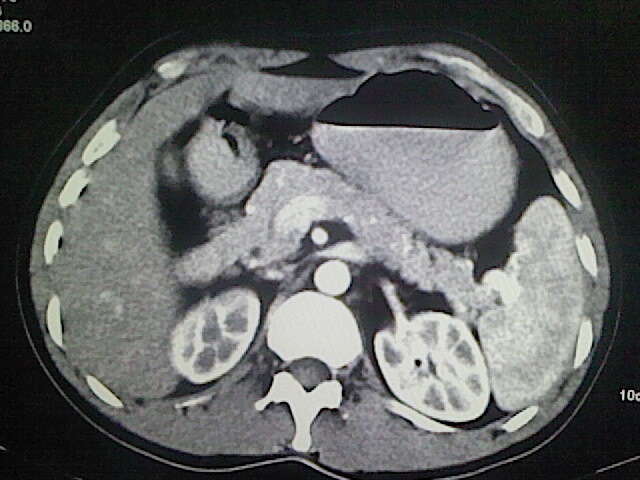

以下是引用卜一在2009-3-14 9:49:00的发言:[br]胆囊萎缩,胆囊壁不规则增厚,内部结构模糊,增强明显强化。另:肝左叶外侧段肝囊肿。支持:慢性胆囊炎!高度可疑:胆囊癌!

以下是引用余辉在2009-3-14 8:48:00的发言:[br]1)慢性胆囊炎。2)肝左叶外侧段肝囊肿。3)脂肪肝。[br]支持,胆囊萎缩,密度增高,不知b超具体有何提示,钙胆汁?结石?

以下是引用jiangjing在2009-3-14 10:18:00的发言:[br]1)慢性胆囊炎。2)肝左叶外侧段肝囊肿。3)脂肪肝。4.】建议行肝功能检查